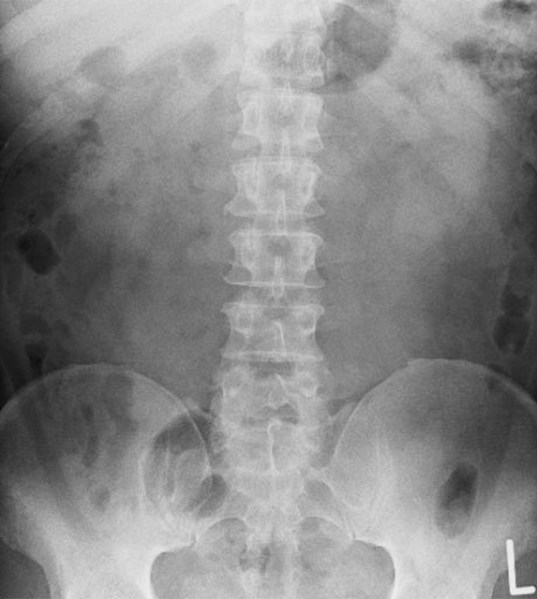

レントゲンを撮影して、診断は「鞭打ち」ということです。処置室に廻されポリネックを巻かれやっと首が座るようになりました。あまりの首の痛さに気を取られそれまで気がつかなかったのですが右足を引きずっていることに気付きます。右足が思うように動かないのですが打った形跡がない。もう一度診察室に戻って足を見てもらい体の各所のレントゲン写真を撮り出てきた診断が「椎間板ヘルニア」。

当時CTのある病院は多かったもののMRIのある病院は少なく、レントゲン写真だけで診察をしていたものでしたが、正面撮影で下から5番目の椎間板が斜めになっていることから、下がっているほうにヘルニアが発生しているという診断でした。専門医はすごい!